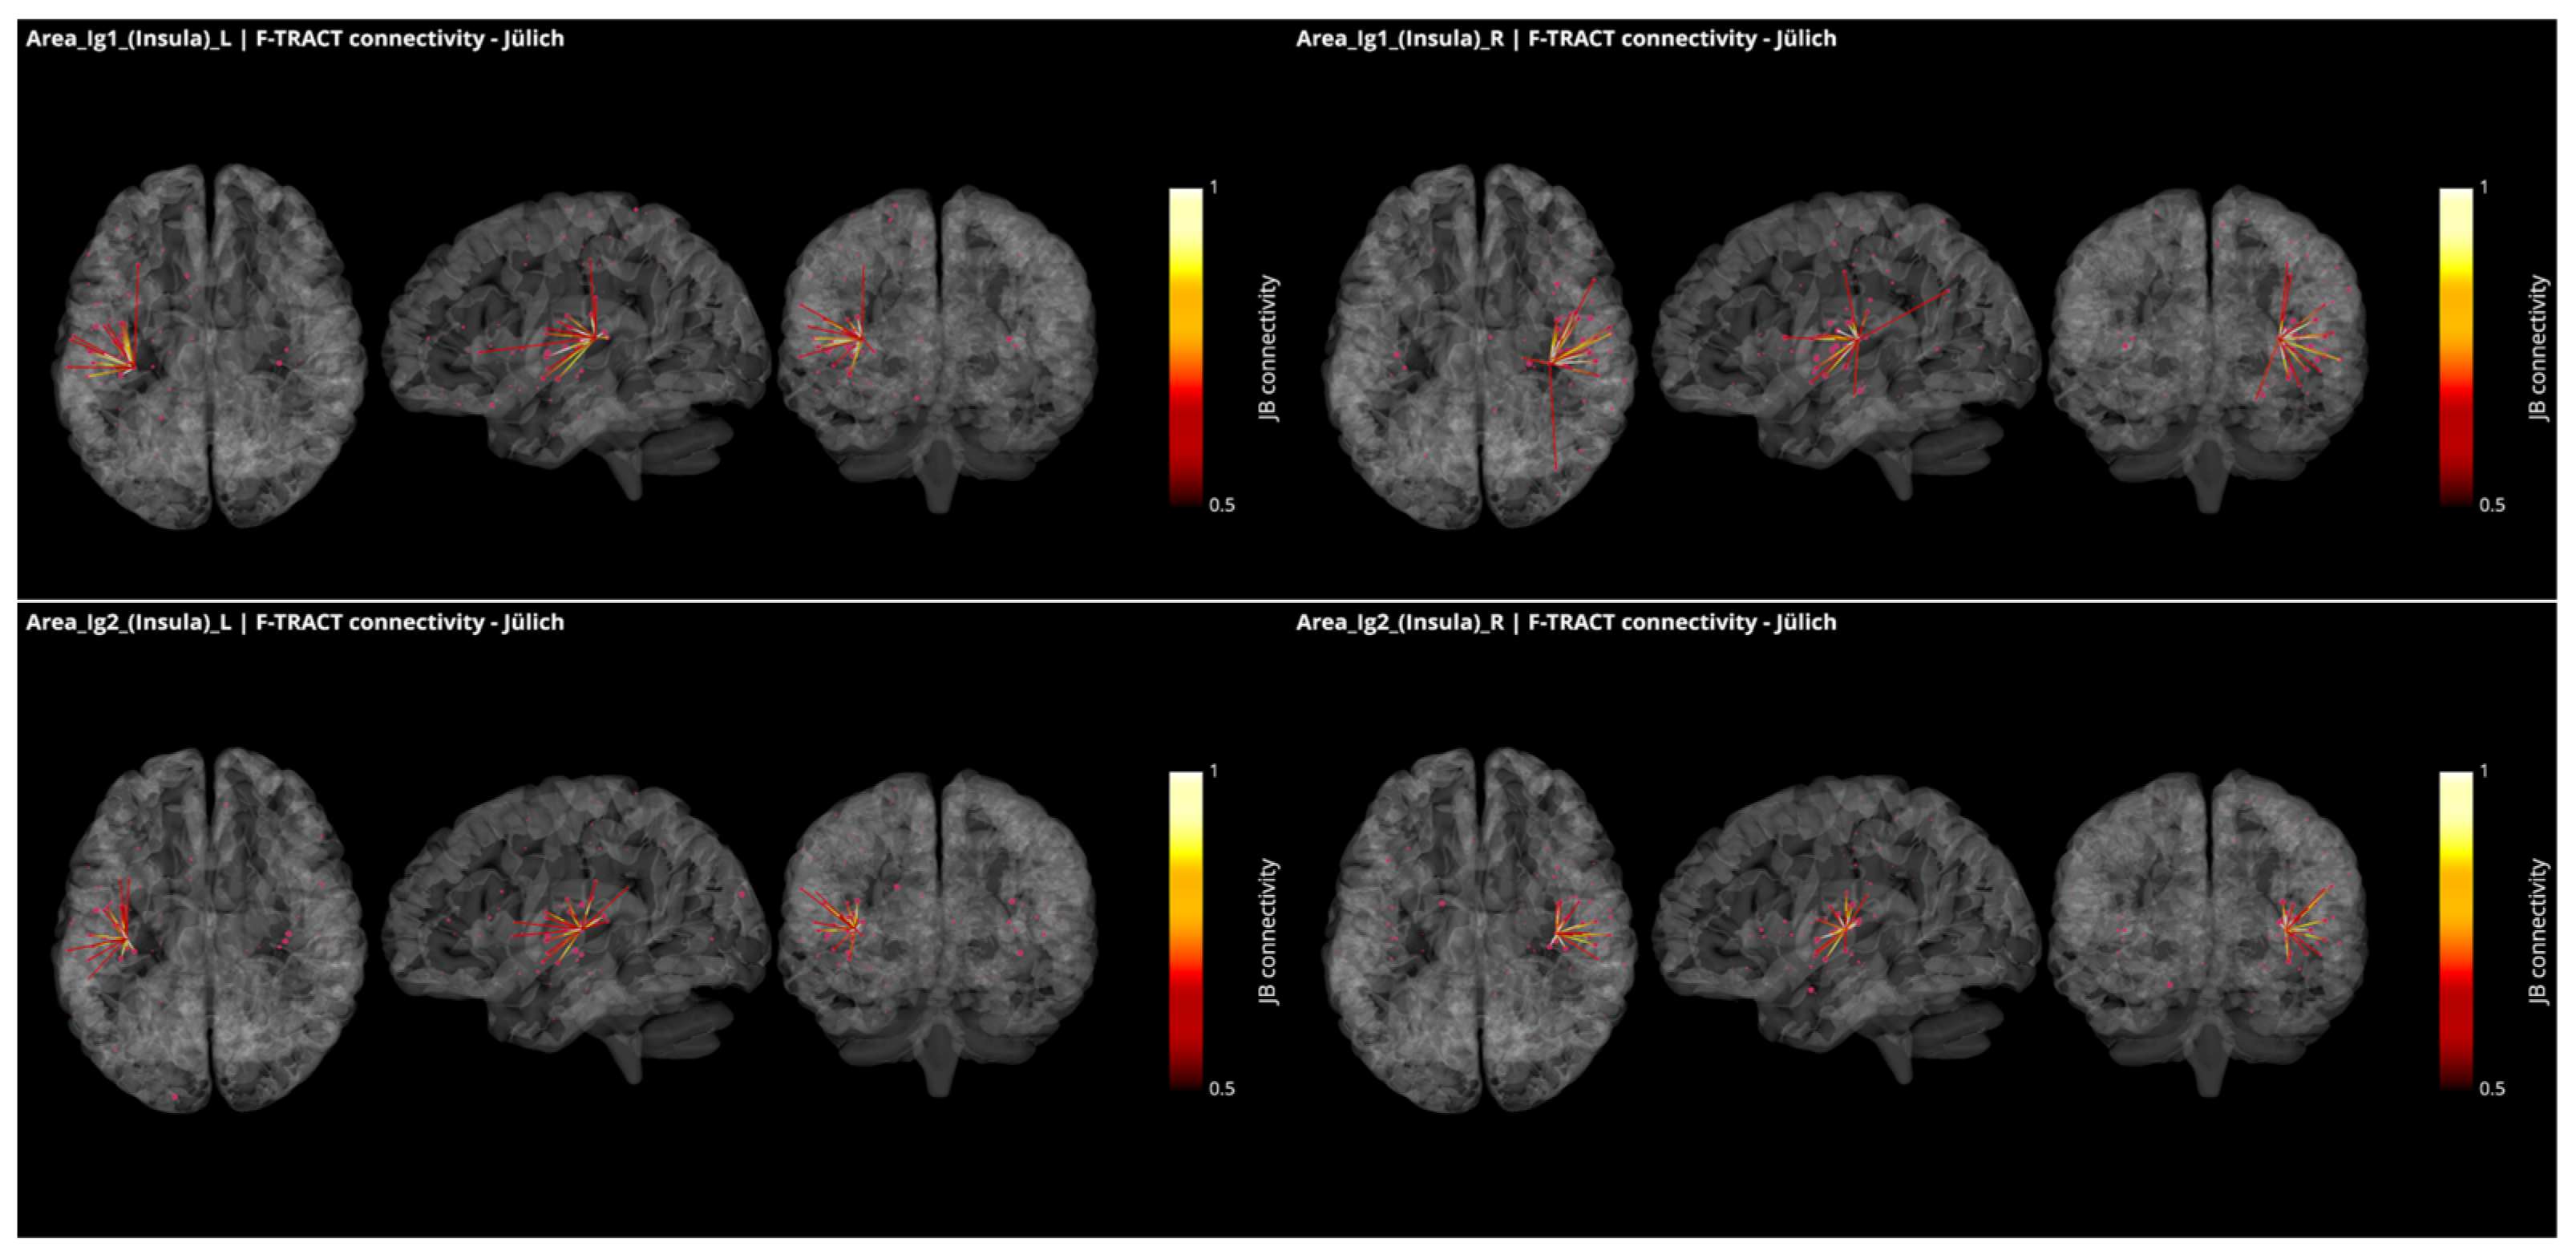

3.3. Operculo–Insular Connectivity

4.2. Functional and Structural Connectivity of the Parietal Operculum and Insular Cortex

- Trebaul, L.; Deman, P.; Tuyisenge, V.; Jedynak, M.; Hugues, E.; Rudrauf, D.; Bhattacharjee, M.; Tadel, F.; Chanteloup-Foret, B.; Saubat, C.; et al. Probabilistic functional tractography of the human cortex revisited. Neuroimage 2018, 181, 414–429. [Google Scholar] [CrossRef]

- Lemaréchal, J.-D.; Jedynak, M.; Trebaul, L.; Boyer, A.; Tadel, F.; Bhattacharjee, M.; Deman, P.; Tuyisenge, V.; Ayoubian, L.; Hugues, E.; et al. A brain atlas of axonal and synaptic delays based on modelling of cortico-cortical evoked potentials. Brain J. Neurol. 2021, awab362. [Google Scholar] [CrossRef]

- Kurth, F.; Zilles, K.; Fox, P.T.; Laird, A.R.; Eickhoff, S.B. A link between the systems: Functional differentiation and integration within the human insula revealed by meta-analysis. Brain Struct. Funct. 2010, 214, 519–534. [Google Scholar] [CrossRef]

- Eickhoff, S.B.; Jbabdi, S.; Caspers, S.; Laird, A.R.; Fox, P.T.; Zilles, K.; Behrens, T.E. Anatomical and functional connectivity of cytoarchitectonic areas within the human parietal operculum. J. Neurosci. 2010, 30, 6409–6421. [Google Scholar] [CrossRef]